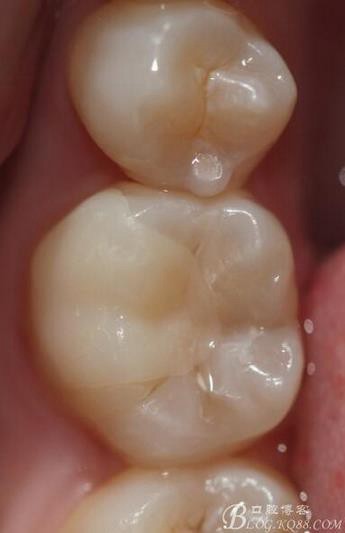

主訴:雙側(cè)下后牙疼痛一月余

病史:近一個月雙側(cè)下后牙疼痛,自發(fā)性 陣發(fā)性鈍痛,進食嵌塞加重,求診

查:雙側(cè)下6頰HE面齲壞 探診疼痛 冷熱刺激 遲反應疼痛 叩診(-)頰側(cè)齲壞平齦

X線:雙側(cè)下6 齲壞已接近髓腔

診斷:雙側(cè)下6 慢性牙髓炎

治療方案:雙側(cè)RCT+CAD-CAM

這里我單做右側(cè)的詳細步驟

根管治療完之后,樹脂墊底,不需要加樁 不管你是做樹脂嵌體還是瓷嵌體。

牙體根充完制備 ,剩余的牙體組織最小的厚度為2mm。